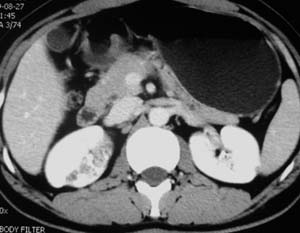

以下是引用子期在2010-3-19 20:47:00的发言:[br]血管畸形的ct增强应该有明显强化,本例并不相符合。本例双肾局部的略低密度影,累及肾盂,局部皮质明显变薄、内陷,增强扫描有轻度的强化,应考虑为炎性病变,患者为年轻男性,累及双肾的感染以结核较常见,可以没有明显的临床症状,尿中有时候也并不能查出什么;肾脓肿常有明显感染中毒症状,本例不符,另外一般的肾盂肾炎或肾小球肾炎通过小便就可确诊,其它还不能排除的是黄色肉芽肿性肾盂肾炎,然而单凭ct一般也很难鉴别。